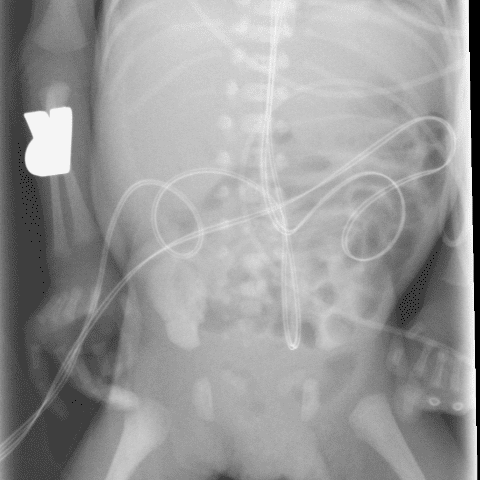

Peds Abdomen

Practice

Simulates call by including subtle or difficult cases and some normals.

30 cases